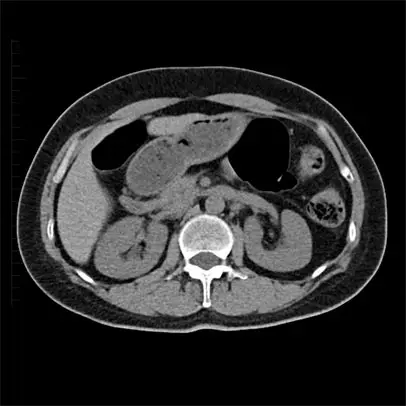

단순 X-ray 촬영부터 초음파, CT를 통해 신장의 형태 및 크기를 파악하여 신장질환의 상태를 확인할 수 있습니다. 조영제는 신장 기능에 영향을 줄 수 있어, 꼭 필요한 경우 예방적인 조치를 하여 안전하게 조영제 CT를 시행하고 있습니다.